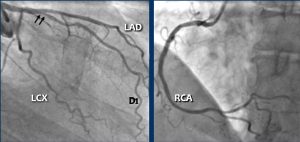

Tiếp tục với các hình ảnh tiếp theo…

Hình A: Chụp động mạch vành xâm lấn (ICA) tương ứng với CTA và cho thấy hẹp 80% ở đoạn giữa LAD (các mũi tên trắng) và hẹp 60% ở nhánh chéo D2 (các mũi tên đen). Hẹp nhánh chéo D2 được ước tính quá mức (overestimated) trên CTA.

Hình B: Can thiệp động mạch vành qua da (PCI) đã được thực hiện trong đó stent phủ thuốc (DES – drug-eluting stent) đã được đặt vào với kết quả tốt (các mũi tên trắng).

Hình A: Hình ảnh MPR cong của LAD với mảng xơ vữa không vôi hóa gây hẹp trung bình (50-69%).

Hình B: Hình ảnh chụp “góc nhện – spider-view” (LAO caudal) (Left Anterior Oblique – Nghiêng trái trước) về phía chân của tim với hẹp 70% ở LAD đoạn gần. Lưu ý sự hiện diện của động mạch nút xoang nhĩ (SA) xuất phát từ LCX đoạn gần và chạy theo hướng sau.

Hình C: Một stent phủ thuốc (DES) đã được đặt vào LAD đoạn gần với kết quả tốt.